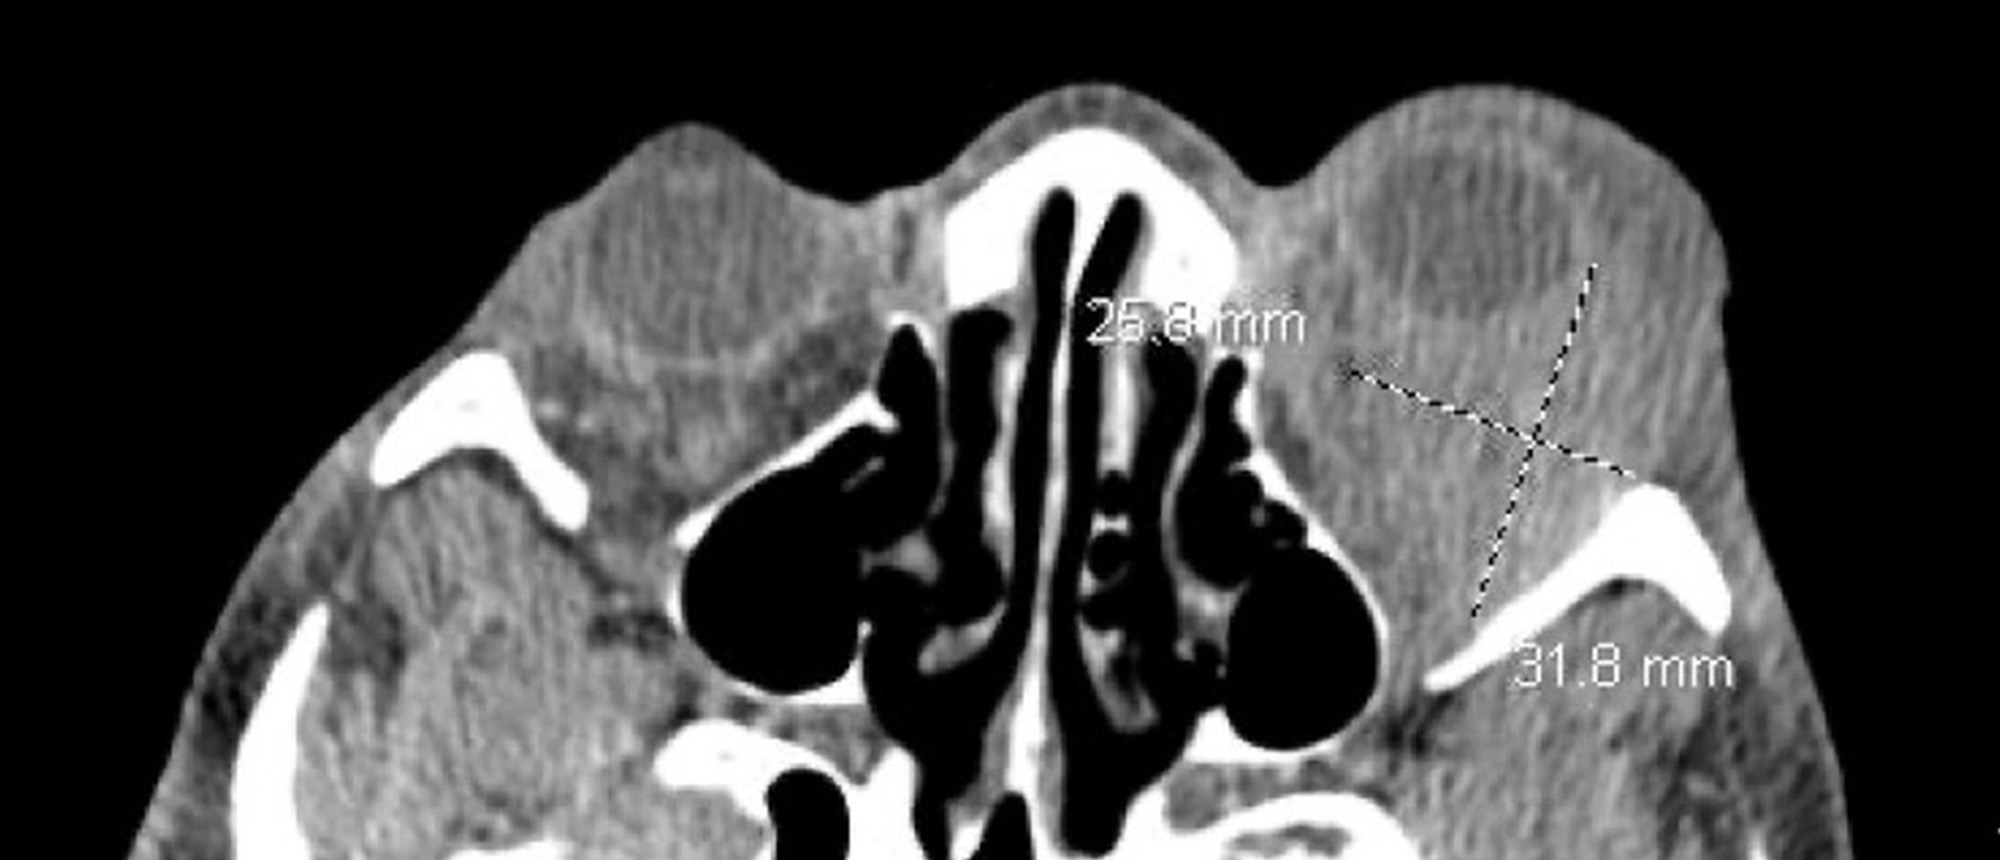

Abstract A patient presented with several weeks of right eye proptosis. On initial examination, his visual acuity in the right eye was 20/400, and a relative afferent pupillary defect was noted. He had 4 mm relative proptosis on the right and restricted motility in all gaze directions. CT orbits re…

NUT Carcinoma A patient presented with several weeks of right eye proptosis. On initial examination, his visual acuity in the right eye was 20/400, and a relative afferent pupillary defect was noted. He had 4 mm relative proptosis on the right and restricted motility in all gaze directions. CT orbi…